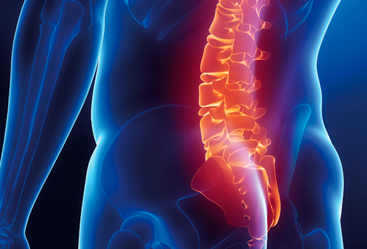

Curitiba – Paraná 29/4/2021 – O procedimento melhora a curva da coluna, possibilitando o ganho de lordose e melhorando o alinhamento da coluna

A cirurgia do ALIF oferece a possibilidade de remover muito mais disco, fazendo com que se tenha grande área para que a fusão entre as vértebras aconteça, diminuindo a complicação de falha da cirurgia e agilizando o retorno às atividades que se deseja realizar. Por meio desta técnica é possível tratar os problemas de deformidade e desalinhamento da coluna e é capaz de descomprimir as estruturas nervosas pela remoção direta do disco, bem como através do aumento do espaço discal, causando o que é chamado de descompressão indireta.

O procedimento melhora a curva da coluna, possibilitando o ganho de lordose e melhorando o alinhamento da coluna. Ajuda assim a poupar o desgaste de outras áreas da coluna.